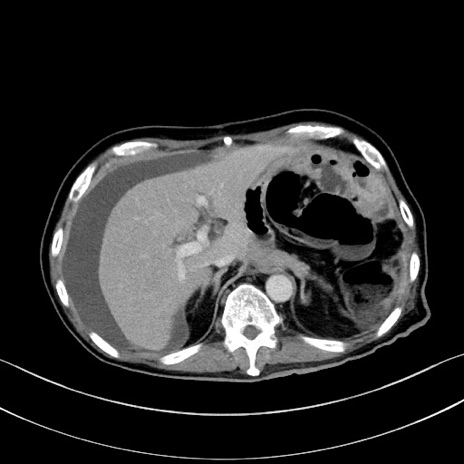

冠状断像

【症例】60歳代男性

【主訴】嘔吐

【現病歴】胃癌にて胃全摘後。食思不振が悪化し、夜中に嘔吐することがある。

【既往歴】胃癌、胃全摘、脾摘、胆摘後

【データ】WBC 5900、CRP 10.56